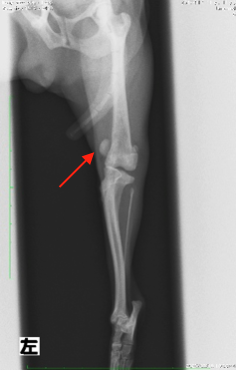

2.X線検査

X線画像を撮影し、脱臼方向の確認や大腿骨と脛骨の骨格変形の有無、変形性膝関節症及び前十字靭帯断裂の併発の有無を確認します。

本症例の術前X線検査所見

本症例は触診と合わせ、膝蓋骨内包脱臼GradeⅡ:症状ありと診断致しました。